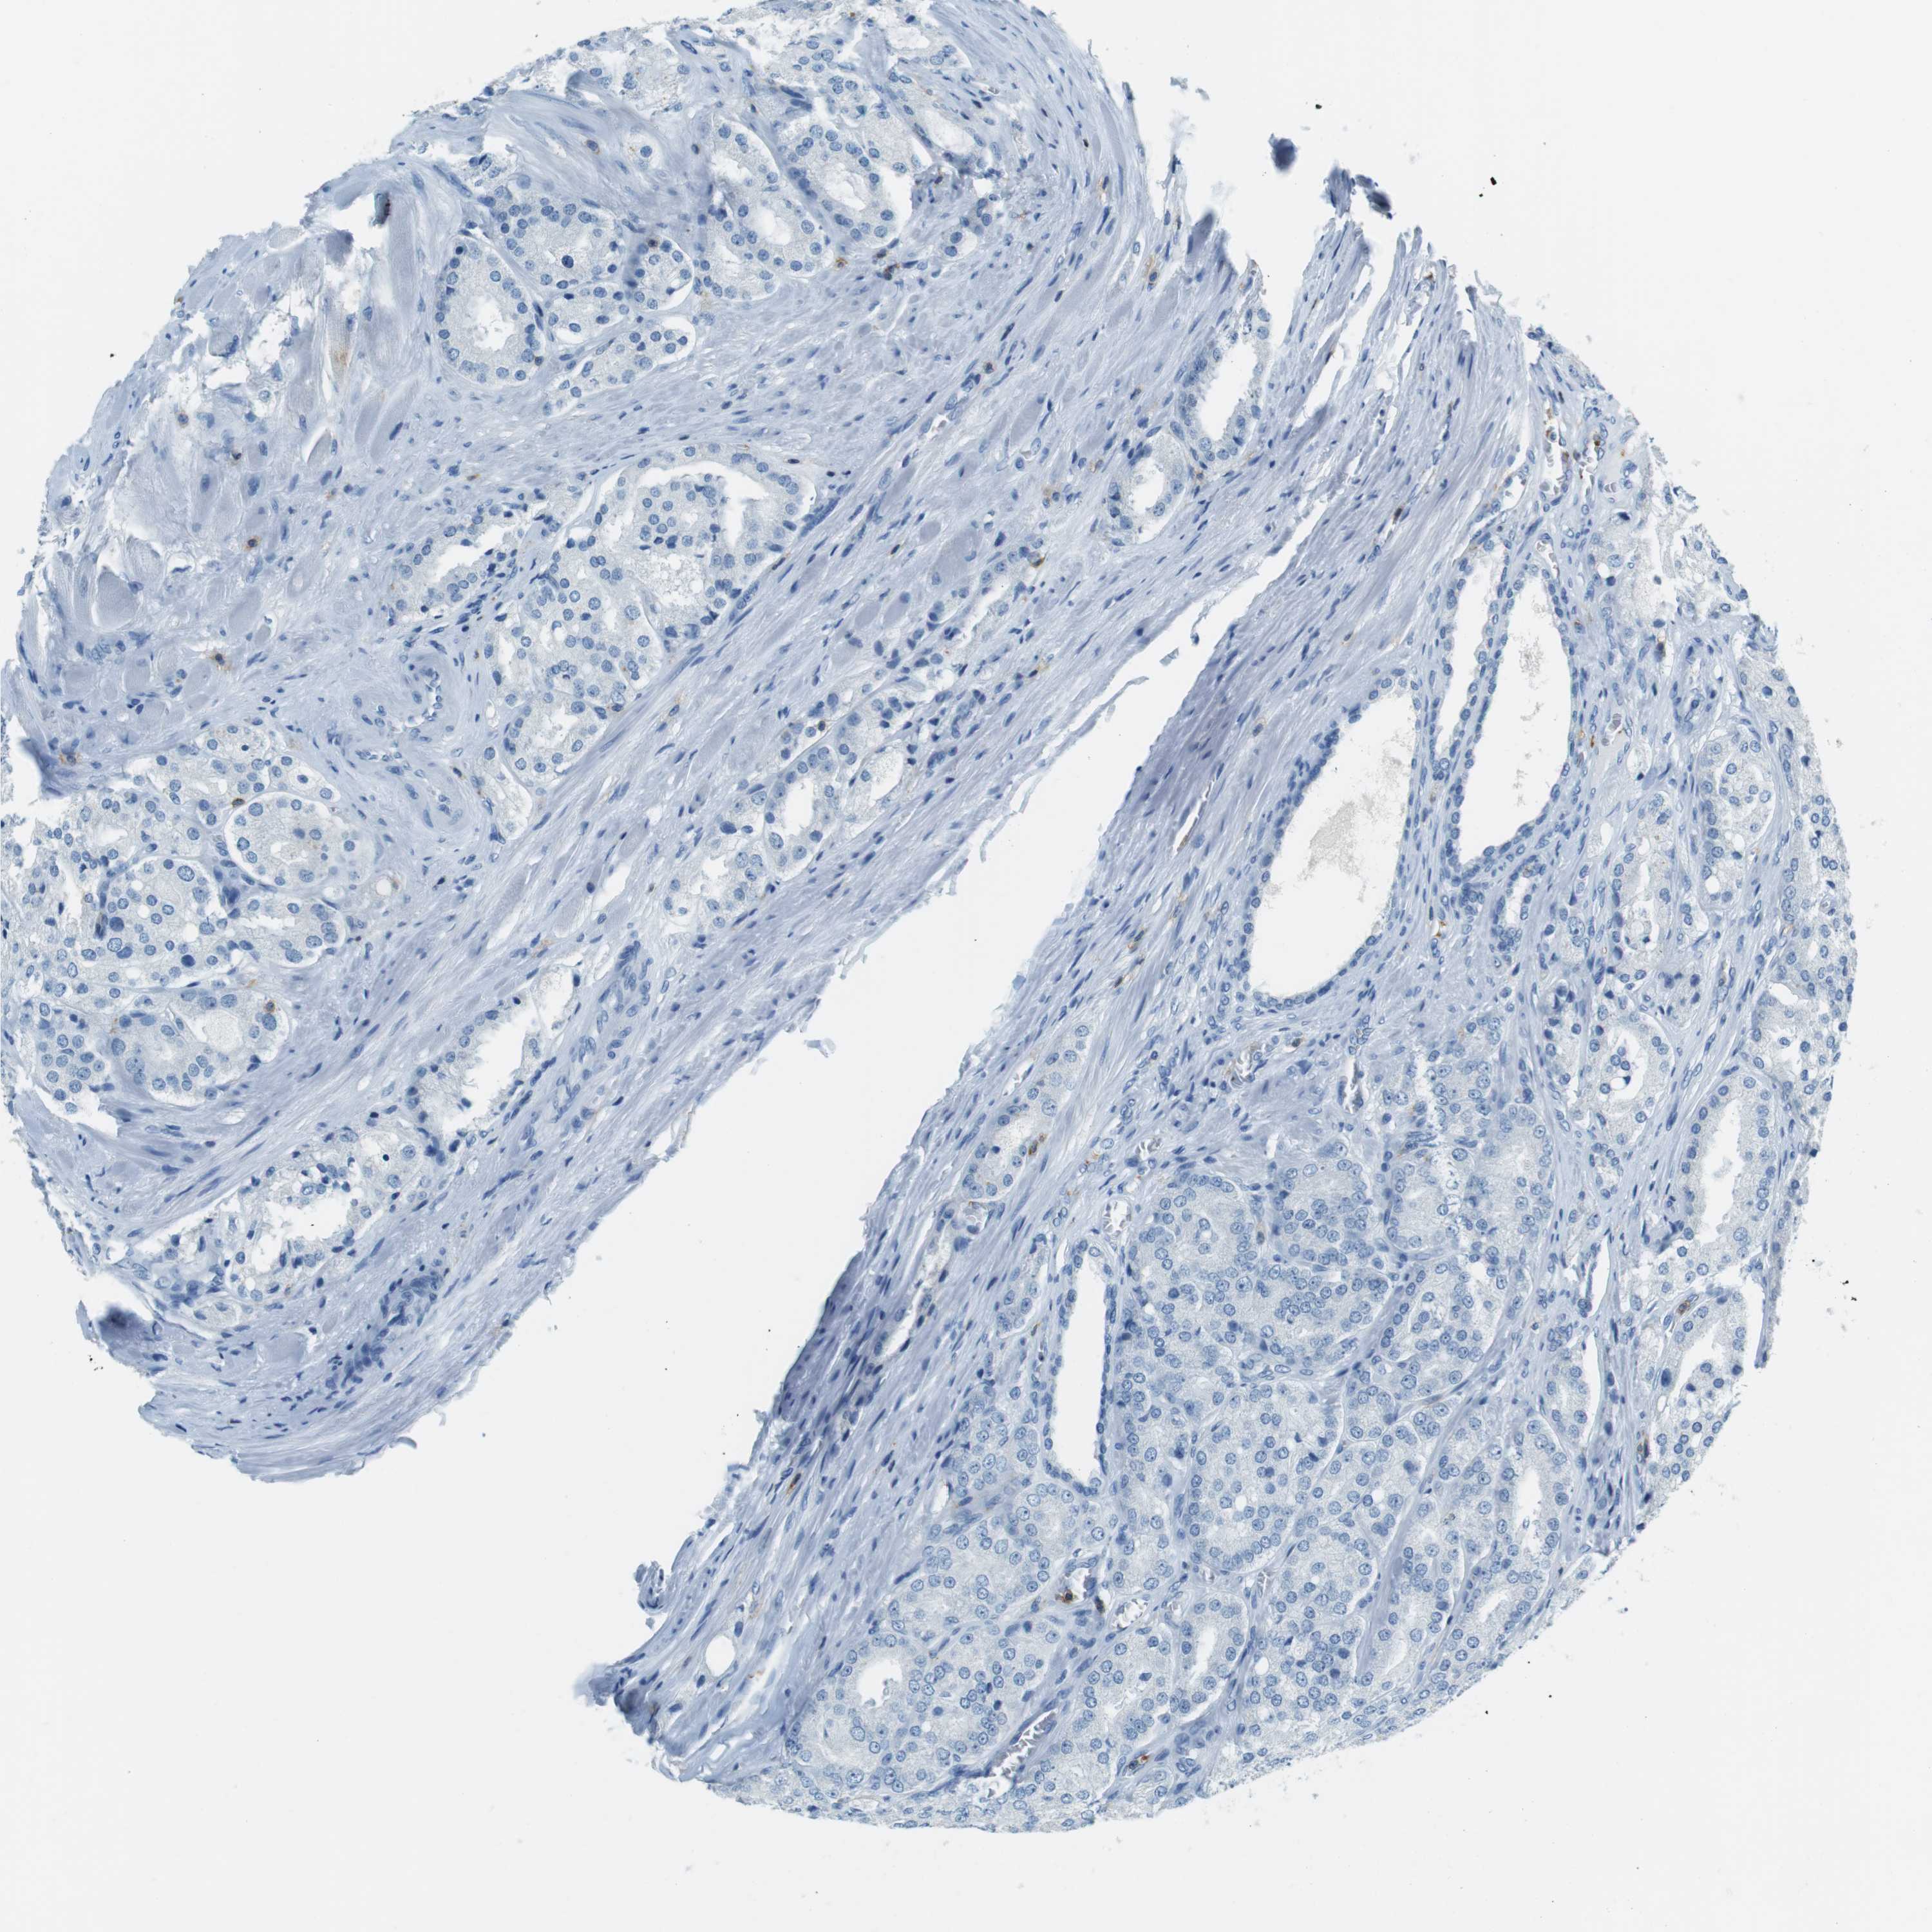

PROSTATE CANCER - Protein expressioni

A mouse-over function shows sample information and annotation data. Click on an image to view it in a full screen mode. Samples can be filtered based on level of antibody staining by selecting one or several of the following categories: high, medium, low and not detected. The assay and annotation is described here.

Antibody stainingi

Antibody staining in the annotated cell types in the current human tissue is reported as not detected, low, medium, or high, based on conventional immunohistochemistry profiling in selected tissues. This score is based on the combination of the staining intensity and fraction of stained cells.

Each image is clickable and will lead to virtual microscopy that enables deeper exploration of all samples and also displays staining intensity scores, fraction scores and subcellular localization as well as patient and tissue information for each sample.

Antibody HPA011157

Antibody CAB002223

Antibody CAB012978

Antibody CAB079960

Staining

High

Medium

Low

Not detected

Intensity

Strong

Moderate

Weak

Negative

Quantity

>75%

75%-25%

<25%

None

Location

Nuclear

Cytoplasmic/membranous

Cytoplasmic/membranous,nuclear

Adenocarcinoma, Low grade

Adenocarcinoma, High grade

Adenocarcinoma, Medium grade

Adenocarcinoma, NOS